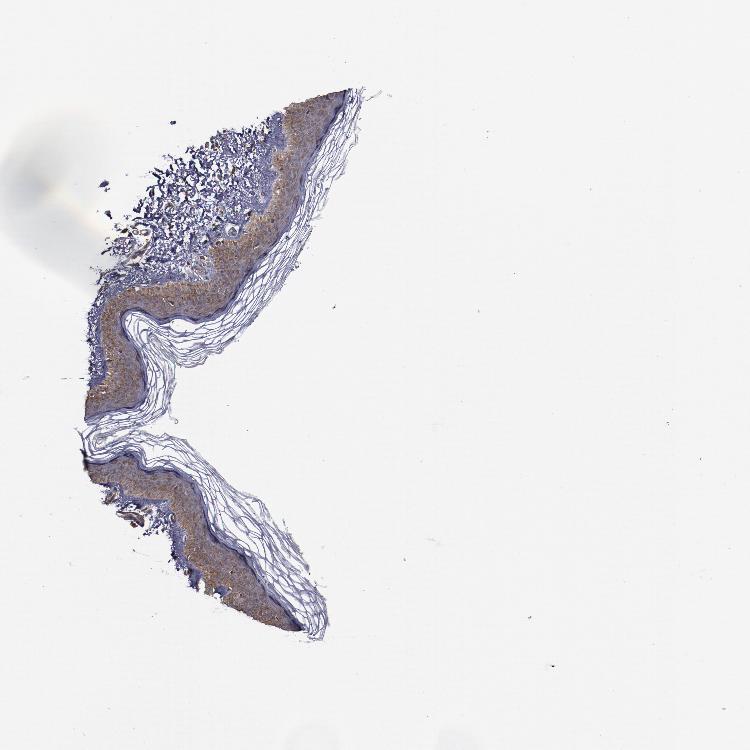

SKIN 1 - Antibody stainingi

Antibody staining in the annotated cell types in the current human tissue is reported as not detected, low, medium, or high, based on conventional immunohistochemistry profiling in selected tissues. This score is based on the combination of the staining intensity and fraction of stained cells.

Each image is clickable and will lead to virtual microscopy that enables deeper exploration of all samples and also displays staining intensity scores, fraction scores and subcellular localization as well as patient and tissue information for each sample.

Antibody HPA000857

Langerhans Medium

Fibroblasts Not detected

Keratinocytes Medium

Melanocytes Not detected

SKIN 2 - Antibody stainingi

Epidermal cells High